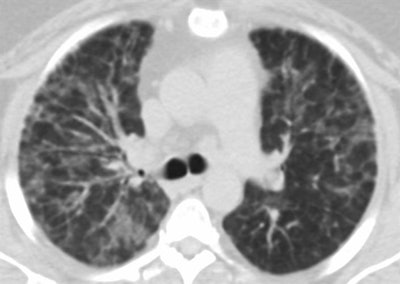

- Hypersensitivity pneumonitis: Findings on CT include symmetric upper lung-predominant and midlung-predominant ground-glass opacity, poorly defined centrilobular nodules, and sometimes attenuation that suggests air trapping.

- Organizing pneumonia: This is characterized by fibroblast proliferation and collagen deposition, and typical CT findings are bilateral patchy ground-glass opacity, consolidation, or both in peripheral or perilobular distribution, according to the researchers.